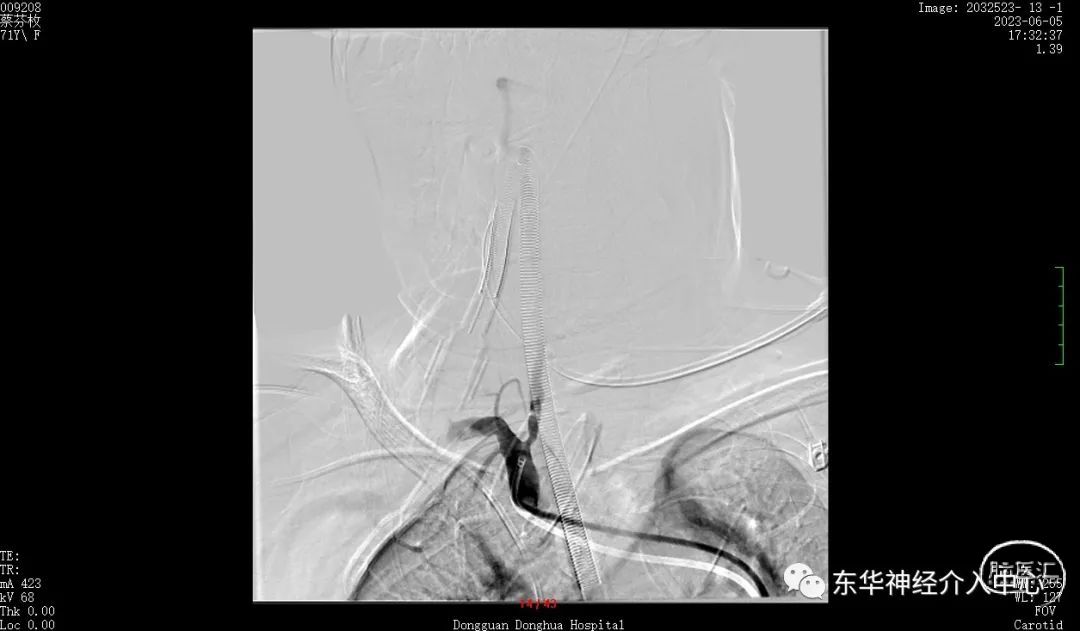

同侧椎动脉的开口狭窄,置入中间导管后血流不通畅。不得不进行开口的扩张。这倒是简单。扩张后顺利将中间导管置入合适位置。开始进行真正的动脉瘤栓塞术。

但是换用了三种微导丝都是难以将微导丝进入到PICA 的远端。考虑可能是动脉瘤稍远的PICA 内有斑块阻挡。微导丝不能到达远端,支架导管就不能进入其内,采取支架辅助栓塞动脉瘤已经不现实了。但是手术不可能放弃呀。曾经也拜读过有同道的文章采取微导丝来辅助栓塞动脉瘤、只能尝试一下了,但是风险更大、难度更高。不过令人欣慰的是经过反复的调整,第一个成篮圈非常满意。